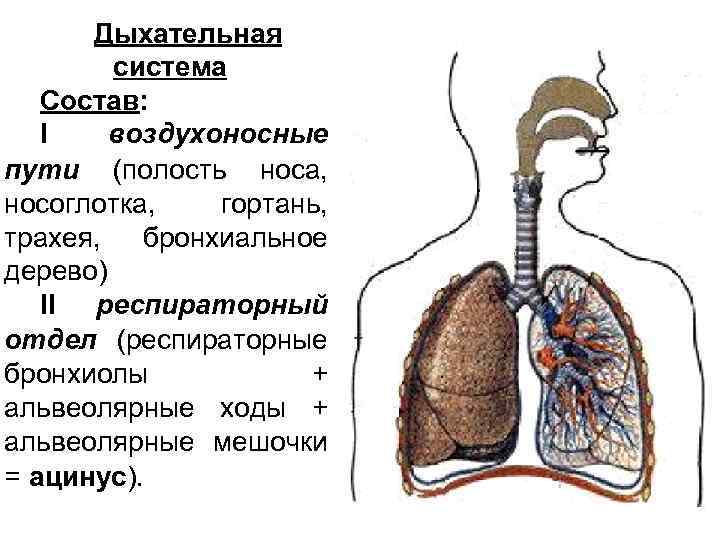

Дыхательная система Состав: I воздухоносные пути (полость носа, носоглотка, гортань, трахея, бронхиальное дерево) II респираторный отдел (респираторные бронхиолы + альвеолярные ходы + альвеолярные мешочки = ацинус).

Воздухоносные пути Функции 1. Проведение воздуха к респираторному отделу 2. Кондиционирование воздуха (согревание, увлажнение и очистка) 3. Барьерно-защитная функция 4. Секреторная функция